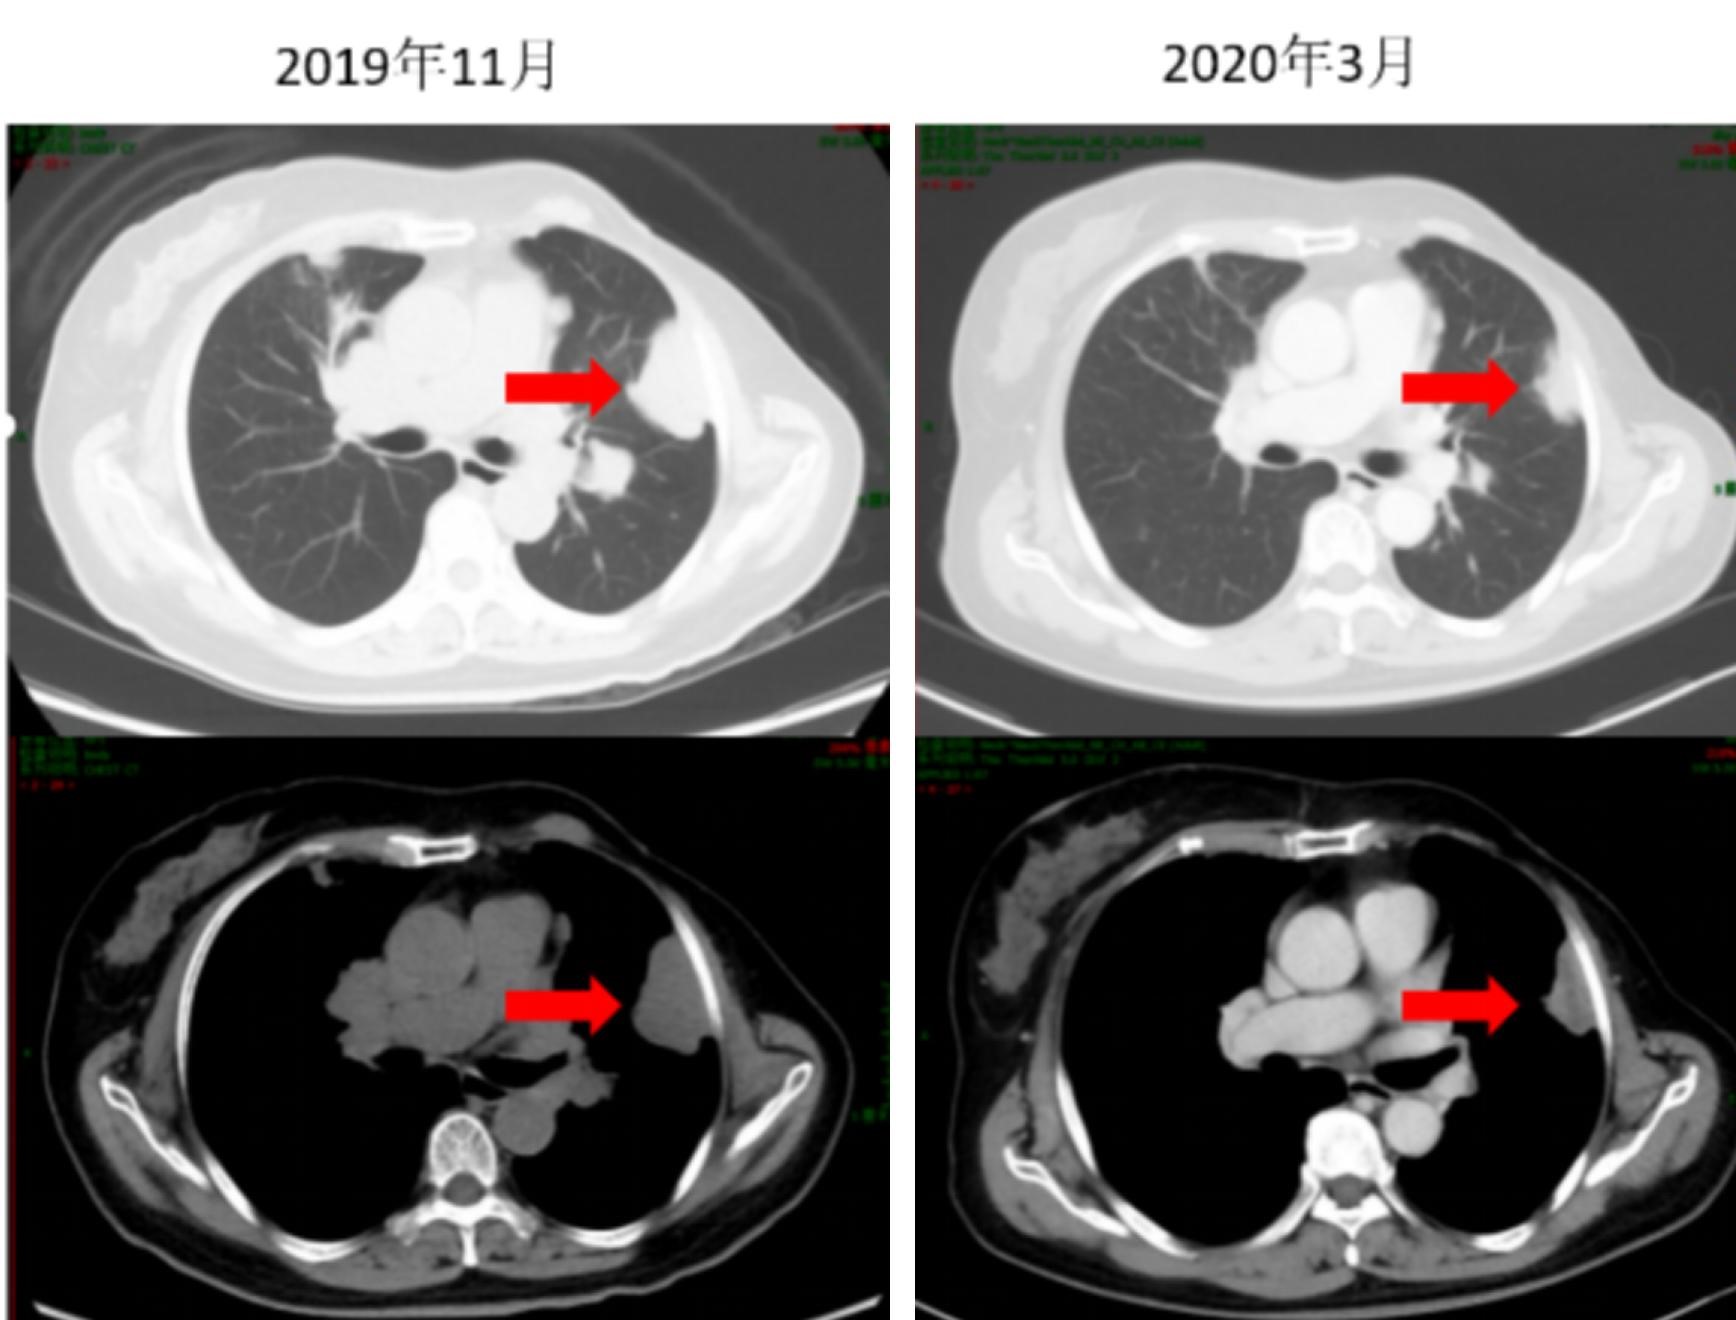

治疗:自2019年11月29日始,进行氟维司群 500mg 皮下注射 第1天 + 长春瑞滨软胶囊 100mg口服  第1,8,15天(每28天一周期,每2-3周期复查,至今共行32周期治疗),唑来膦酸 4mg 静脉滴注,每28天1次。

疗效评估:症状体征变化:胸痛及咳嗽逐渐缓解;辅助检查改变:肿瘤标志物逐渐下降(图2,图3);影像学评估:肿瘤较前缩小,评价PR(图4,图5);不良反应:I度恶心及I度呕吐。

图6 CT示胸膜转移灶缩小

图7 CT示胸膜转移灶进一步缩小

随访:患者于2019年11月就诊后行口服长春瑞滨软胶囊+氟维司群联合治疗,至今已行32周期,现CT等检查示疾病控制良好,仍继续当前方案维持治疗和随访中。